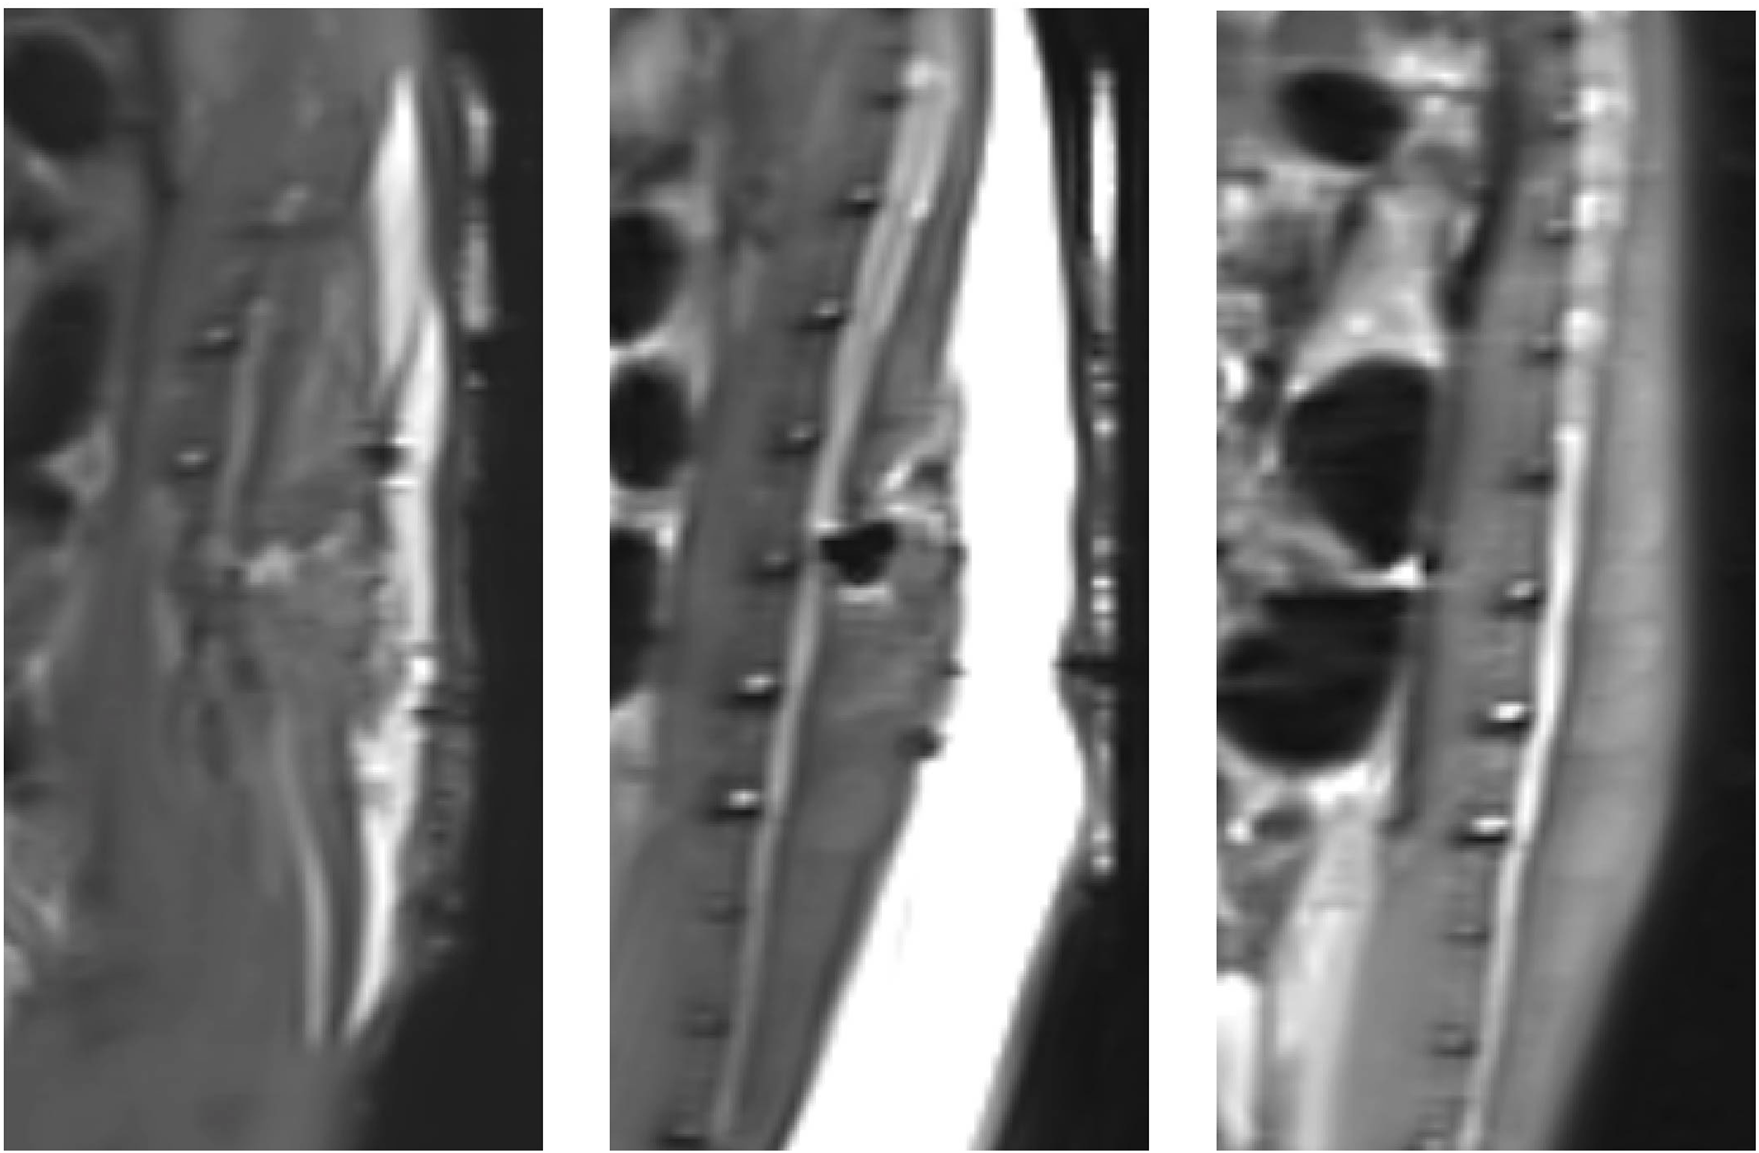

The results of MRI scans of the rat spinal cord after surgery and before surgery are shown in Figure 4. There was no obvious effusion in the spinal cord after operation. This indicated that there was no obvious fluid perfusion in the spinal cord when the dura mater was incomplete.

FIGURE 4

Magnetic resonance imaging results of postoperative rats and preoperative rats (T2): From left to right, the MRI results are shown for rats in group A, rats in group B, and rats that did not undergo surgery.